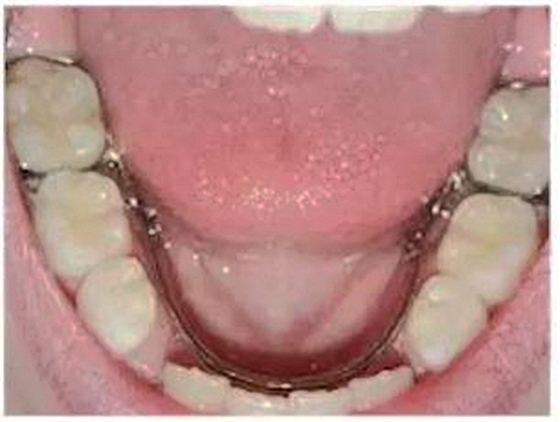

②舌弓式間隙保持器

乳牙缺失致恒牙“亂長”,這個“間隙保持器”可預防

這種間隙保持器用于下牙左右兩側(cè)都有缺牙的情況,“舌側(cè)”是指牙齒靠近舌頭的那面。這種保持器的兩端固定在兩側(cè)缺失牙后方的牙齒上,一個弓絲沿著下牙的內(nèi)側(cè)連接兩段的帶環(huán)。